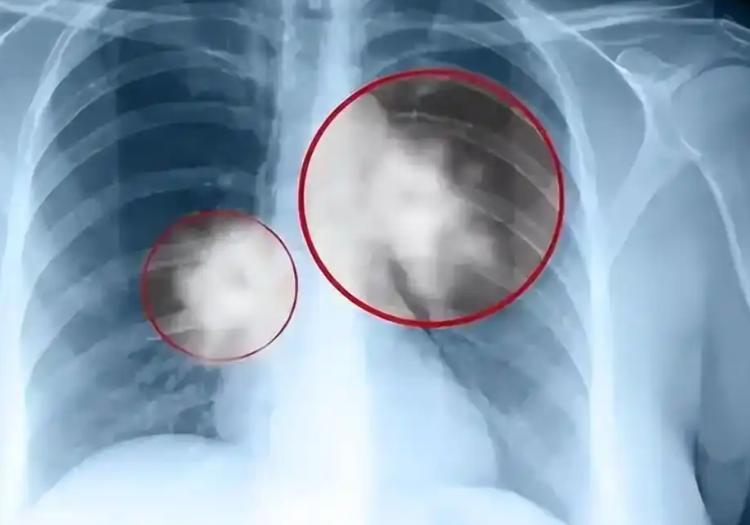

肺部有结节的人,身上基本有这4个表现,千万注意

肺部疾病有一个让人头疼的特点,就是早期症状和普通呼吸道问题高度重叠,极难第一时间识别。

反复咳嗽超过三周、用了常规药物也没有改善,这本身就值得认真对待。不是说咳嗽等于大病,而是持续性、无明显诱因的咳嗽在医学上被称为慢性咳嗽,触发原因很多,肺部肿瘤是必须排查的一个选项。

痰中带血这件事,有多少人第一时间重视?数据显示,超过60%的肺癌患者在确诊前都出现过反复咯血或痰中带血丝的情况,但真正第一次发现就去医院的人比例极低。

有人觉得是上火,等几天没再出现就算过去了。但这类出血的背后是肿瘤侵蚀支气管黏膜血管的结果,出现、消失、再出现,这个节律本身就是身体在拉警报。

肺癌早期发现后五年生存率可以达到70%以上,到了晚期这个数字会骤降到不足15%,这个差距足够说明早查的重要性,别等到症状明显到忍不了才行动。